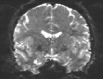

Figure 6: Example field maps (Subject ID 826353) at initialization (top row) and after optimization with Gauss-Newton (bottom row). The first column uses the proposed optimal transport initialization scheme. The middle column uses the same scheme with an additional Gaussian blur to promote smoothness. The right column uses the coarse-to-fine multilevel initialization scheme from HySCO with five levels, and the final field map is optimized at the original image resolution. The multilevel initialized field map is smooth by construction and further optimized to improve the relative image distance at the full resolution. The optimal transport initialization accurately corrects the distortions but is not smooth in the non-distortion dimensions unless blurred with a Gaussian. After the fine-level optimization all field maps are visually similar.